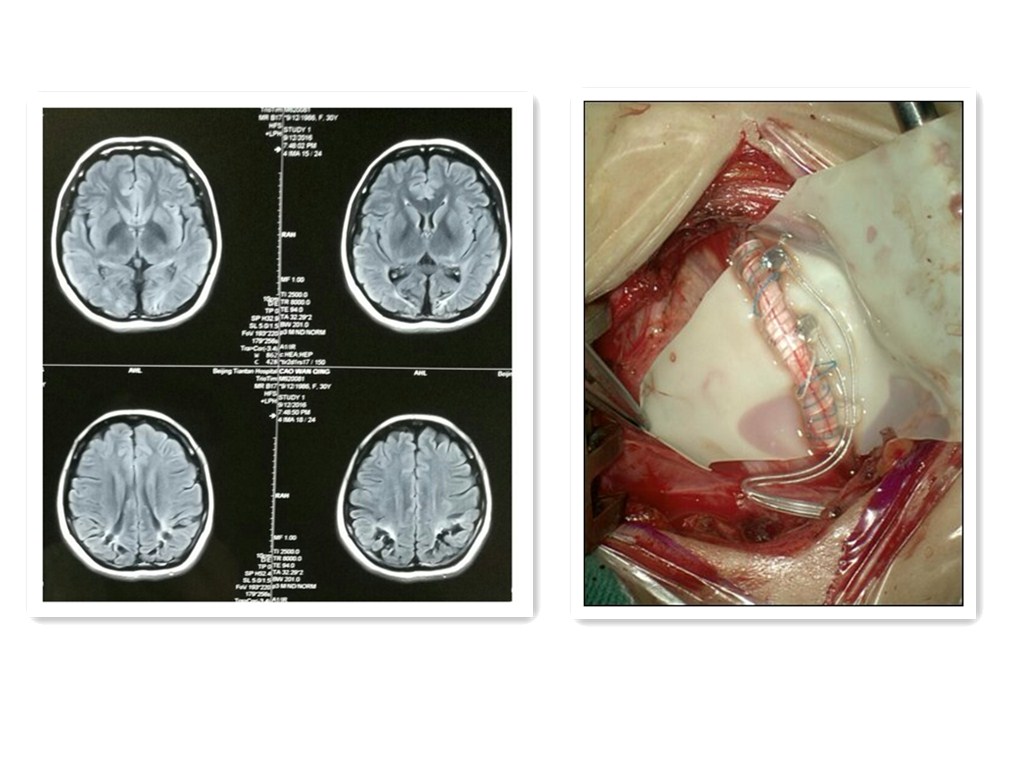

开启刺激器,开始新生活